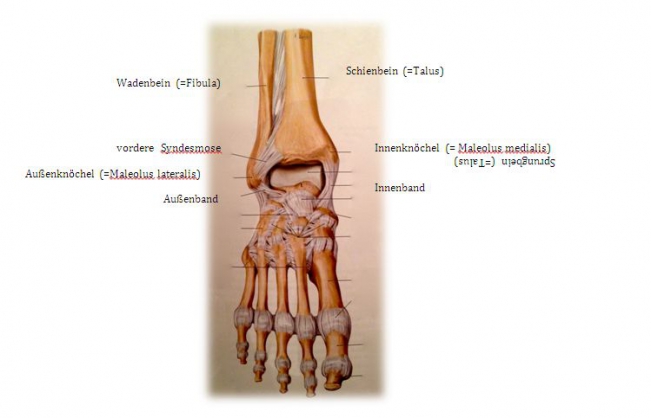

If one speaks of the ankle joint, one actually speaks of the "upper ankle joint". It is formed by three bones: Shin bone (= tibia), fibula and talus. Shinbone and fibula form a bony fork (= malleolus fork), which surrounds the anklebone in a U-shape. The upper ankle joint allows the foot to be raised and lowered.

The outer ankle is the joint process of the fibula, the inner ankle is the joint process of the tibia. A complex ligamentous apparatus ensures the stability of the ankle joint: outer ligaments, inner ligaments and anterior and posterior syndesmosis (= a very firm ligament connection between the tibia and fibula).

Fig.1) Anatomy of the upper ankle joint (from: Prometheus ®, MLP)